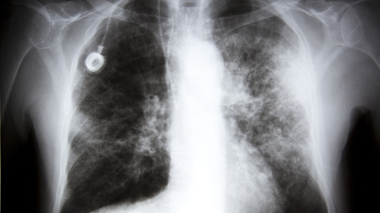

Lung Cancer Picture Image On Medicinenet Com

As the tumors grow in these areas, they may cause localized pain as they push against organs and interfere with normal body functions In the brain, the cancer may cause headaches, drowsiness, confusion and nausea Other common final stage lung cancer symptoms include a lack of sweating, facial swelling due to fluid buildup, fatigue, bone pain The late signs occurred mostly in the last 3 days of life, had lower frequency, and were highly specific for impending death in 3 days Late signs included the following 9 Pulselessness on the radial artery Respiration with mandibular movement Decreased urine output CheyneStokes breathing Death rattle Apnea periods Peripheral cyanosis Patients' characteristics were monitored and documented every 12 hours until hospital discharge or death Fiftyseven percent of patients died at the cancer center after admission The eight most prominent physical signs had a high specificity of more than 95% and occurred in 5% to 78% of patients within their last 3 days of life